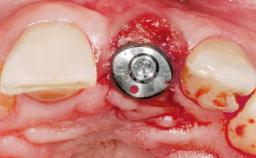

| Attachment | One-Piece |

| Abutment Type | Customized |

| Placement Protocol | Immediate implant placement |

| Tooth Site | Maxillary incisor or canine |

| Socket Morphology | Single-root socket |

| Socket Integrity | Damage to one or more bone walls |